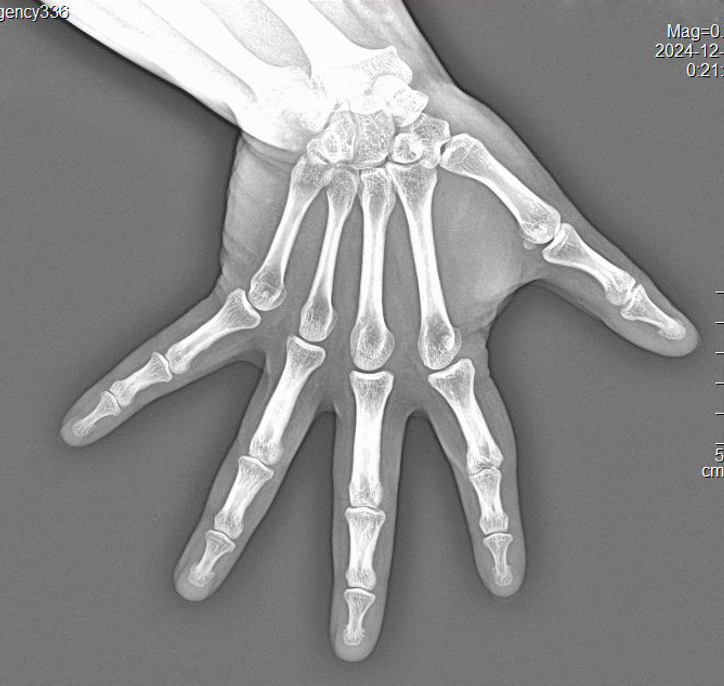

Doctor from Ghana purchased 2pcs wireless flat panel detectors YSFPD-M1717V to upgrade his existing x-ray system, and he is satisfied with the good quality images.